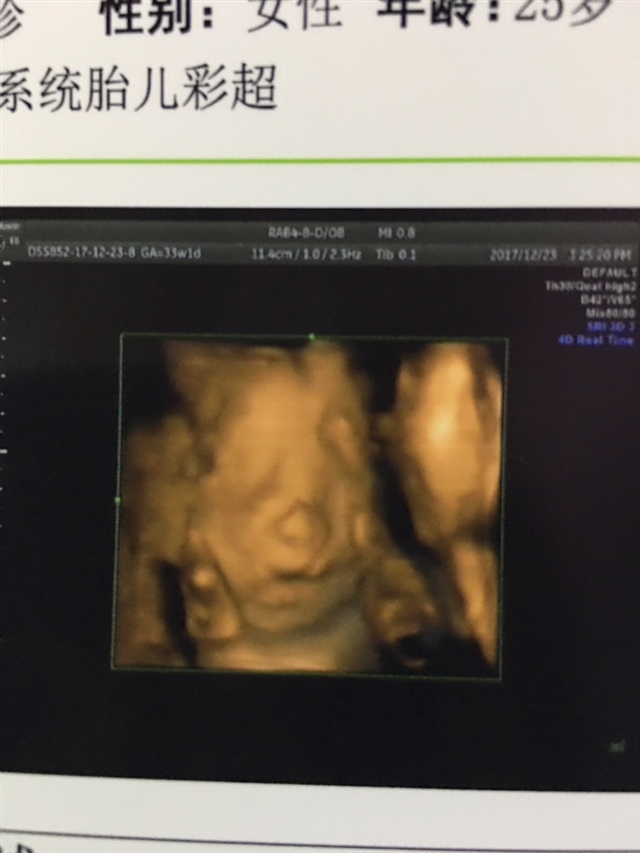

孕29周+5天

女孩